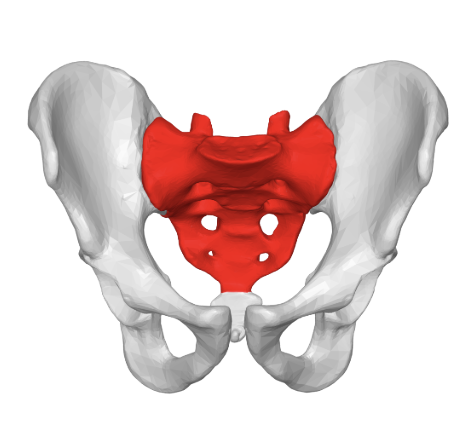

how many bones are in the bony pelvis?

4 bones

what are the bones in the bony pelvis?

sacrum

coccyx

innominate bones (2)

forms part of posterior margin

innominate bones

aka hip bones (consists of ilium, ischium, and pubis)

forms anterior/lateral margin